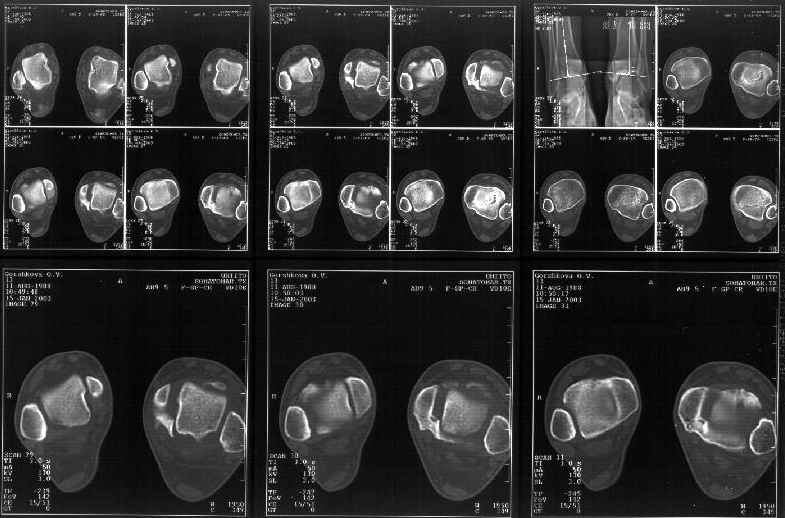

Я пометил линию перелома черной линией.

К сожалению на последних присланных срезах КТ нет более низкого, через таран, среза, который был на прежнем майле. На XR я попытался показать

стержень внутри сустава и то как он раскрывает пространство между тараном и мед. малеолом.

Сегодня пациентке сделали сравнительную КТ. А ксиальные и Фронтальные срезы приложены. Ваше мнение?

Фронтальные

Аксиальные

Спасибо за КТ -она изумительная. К сожалению, я по дороге на врачебный викенд на Мёртвом море и не смогу подготовить комментарий и схемку до 19.01.03 Помоему, результат КТ даёт чёткую возможность красивой и эффективной помощи.

Отправитель: Й. Воск 19 Январь 2003, 22:50

На КТ я попытался изобразить скромными своими способностями (А)- место перелома, (С)- нормальный суставной зазор меж тараном и тремя его маллеолами. (В)- образовавшийся в результате перелома широкий раза в три зазор, позволяющий, по-моему, сублюксацию тарана при ходьбе. В свете данных КТ, критически важных, я бы предложил вертикальную остеотомию места перелома

задне-внутренним подходом и фиксацию мед. маллеола прижатым к тарану с помощью тонкого compression screw. После этого гипсовый сапожок и немедленное расхаживание ноги.